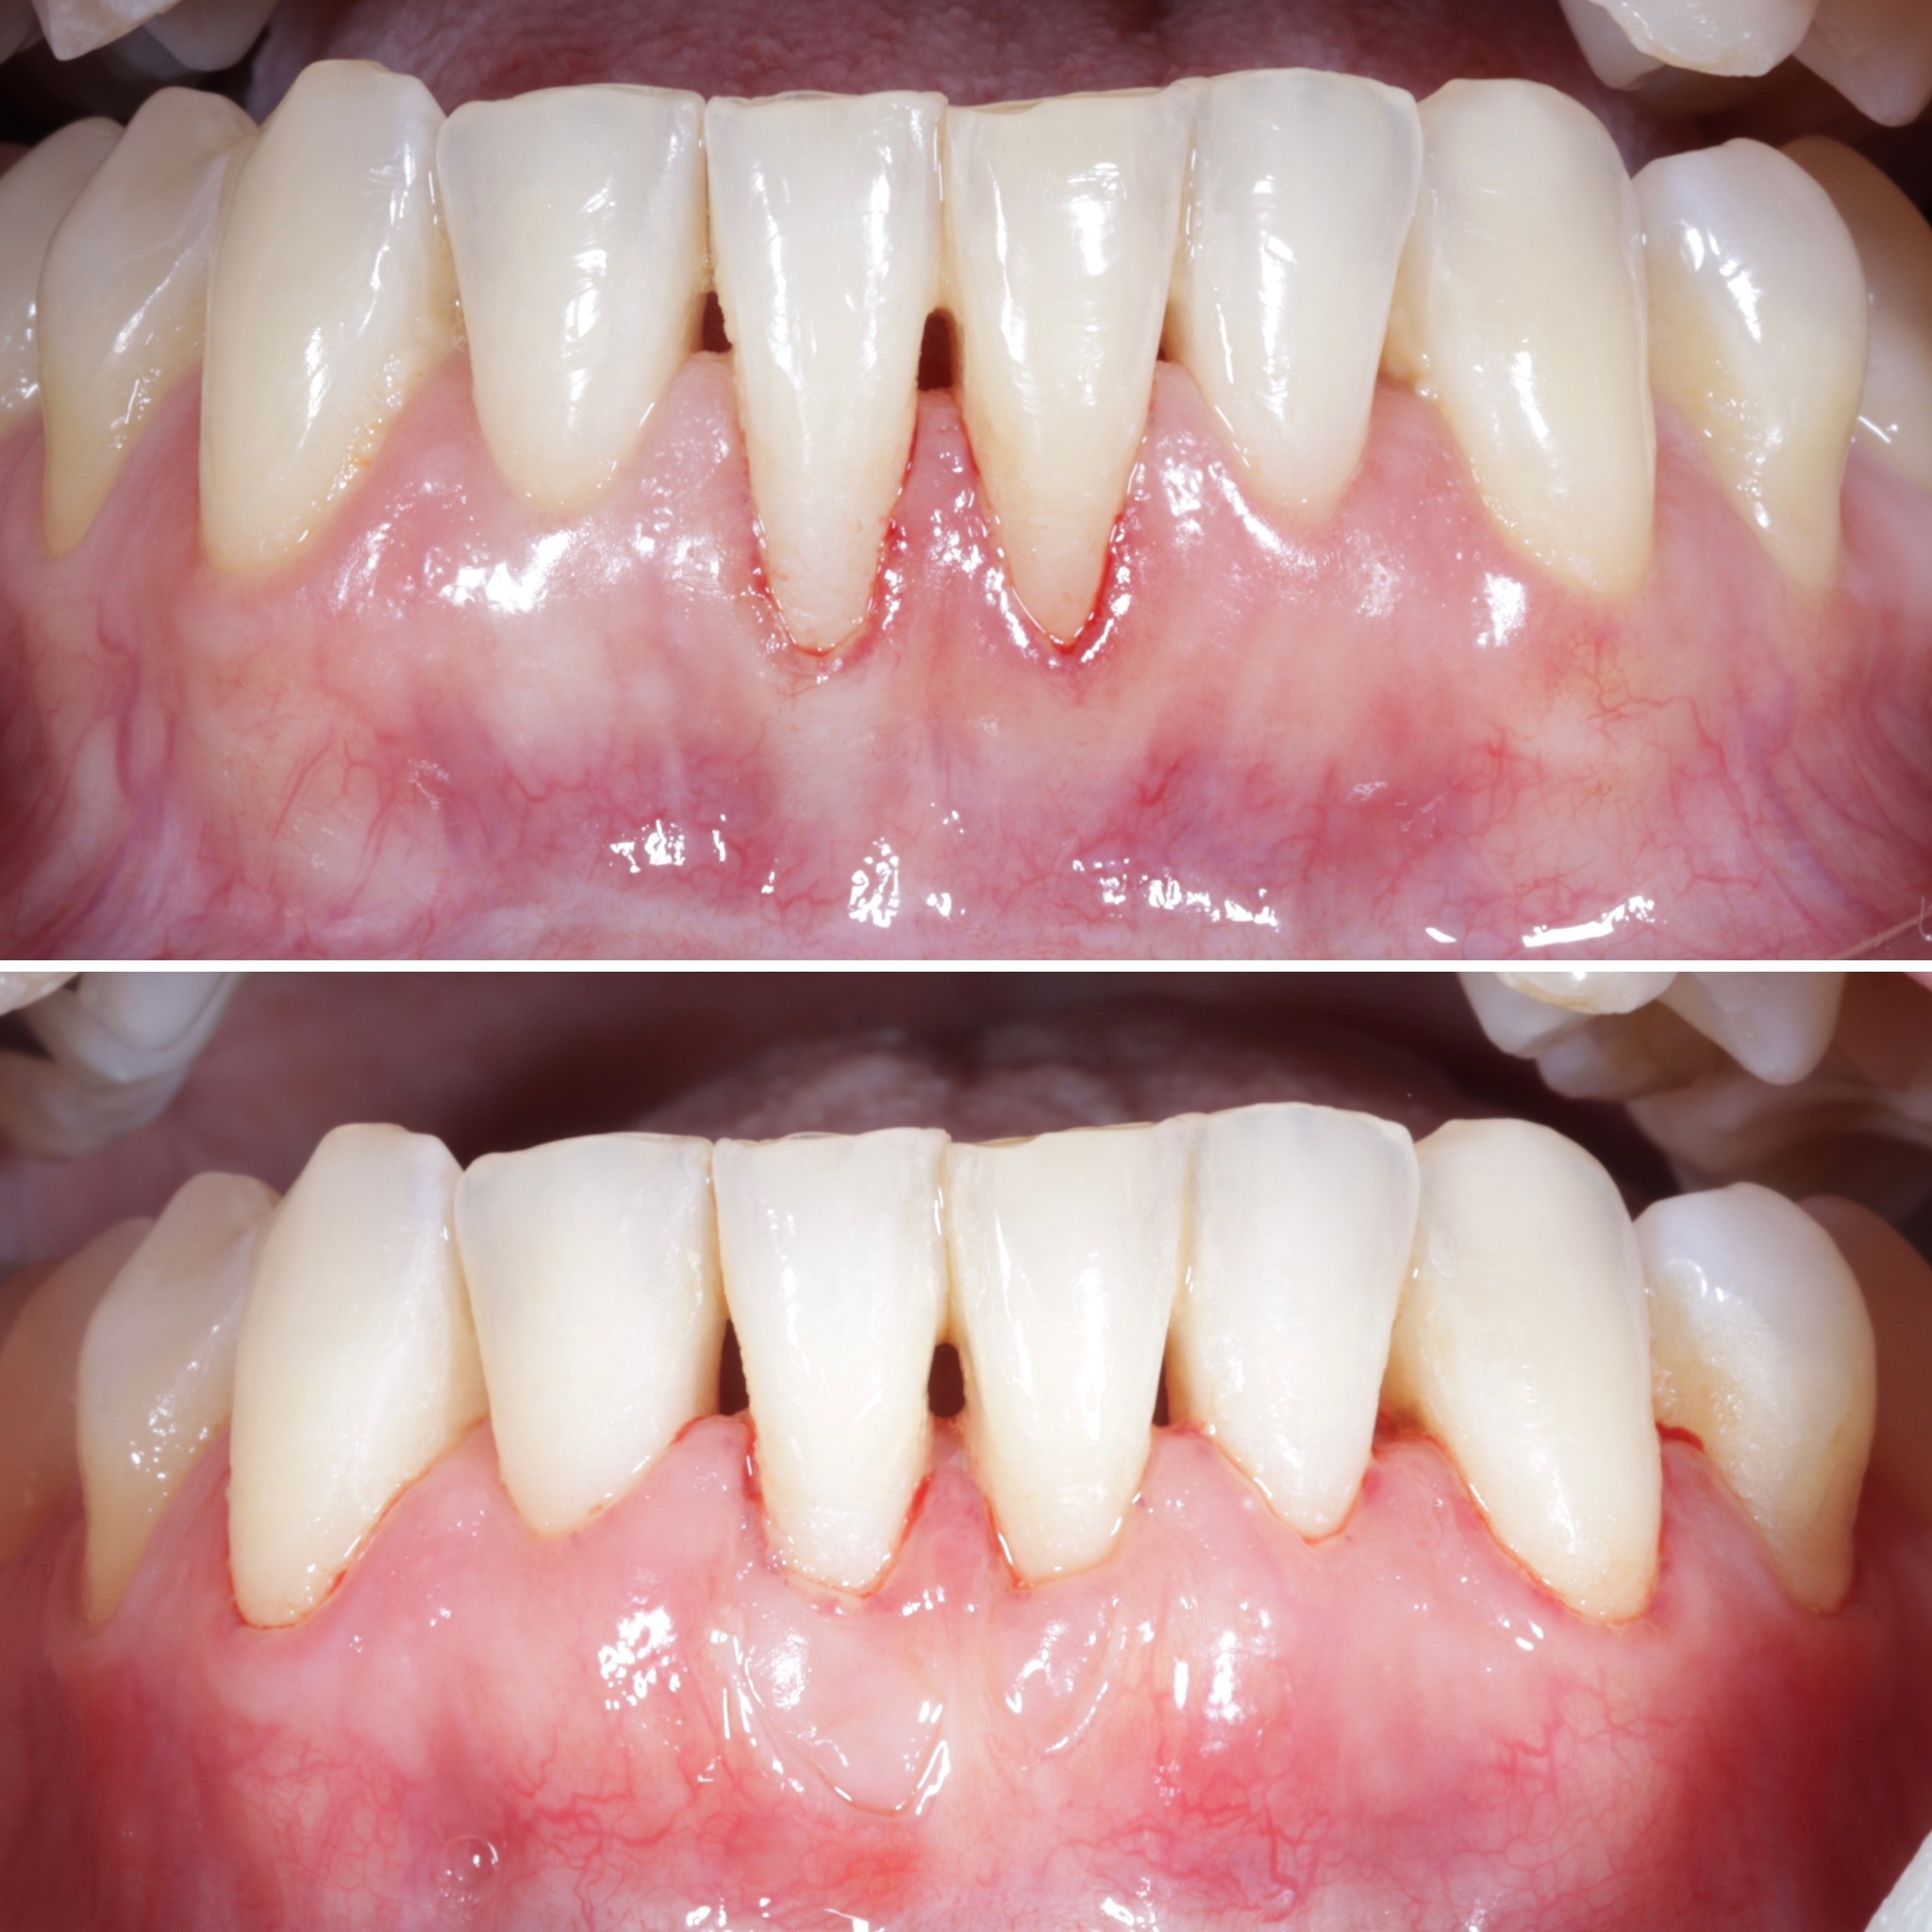

Durante una mañana, asistirás a una Cirugía Mucogingival de recubrimiento radicular de recesiones múltiples en IV y V sextante (36 a 43).

Gracias al uso del microscopio y a la proyección en tiempo real en pantalla, verás exactamente lo mismo que veo yo durante la cirugía, sin tener que estar

Aprende la planificación y técnica de la cirugía Mucogingival para el recubrimiento de recesiones y aumento de banda queratinizada en el sector anteroinferior

Durante una mañana, asistirás a una Cirugía Mucogingival de recubrimiento radicular de una recesión unitaria en 31 con frenillo asociado. Gracias al uso del microscopio y a la proyección en tiempo real en pantalla, verás exactamente lo mismo que veo yo durante la cirugía, sin tener que estar